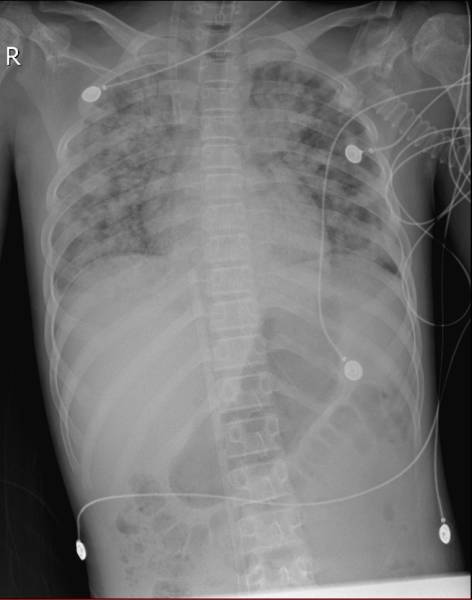

治疗前患儿胸片

检验科室采用操作复杂、技术要求较高、难度较大的六甲基四胺银染色 (GMS) 法检测肺孢子虫包囊。经过一系列繁琐紧张的工作,经验丰富的检验技术人员在显微镜下成功找到耶氏肺孢子虫包囊,并查到了包囊典型的特征性括弧样结构,为临床提供了重要的诊断依据。